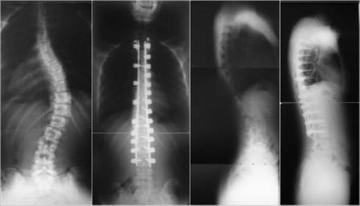

Her bir tür, farklı tedavi yaklaşımları gerektirebilir. İdiyopatik skolyoz, genellikle ergenlik döneminde ortaya çıkar ve tedavi edilmediğinde ciddi sorunlara yol açabilir. Skolyozun TanısıSkolyozun tanısı genellikle fizik muayene ve görüntüleme yöntemleri ile konur. Doktor, hastanın duruşunu değerlendirir ve gerekirse röntgen çekimi yapar. Röntgen, omurganın eğilimini ve açılarını belirlemeye yardımcı olur. Skolyoz Tedavi YöntemleriSkolyoz tedavisinde kullanılan başlıca yöntemler şunlardır:

Fizik Tedavi ve Egzersiz: Fizik tedavi, skolyozun ilerlemesini durdurmak ve postürü düzeltmek için önemli bir rol oynar. Hastalara özel egzersiz programları uygulanır. Bu programlar, kas gücünü artırmayı ve esnekliği geliştirmeyi hedefler. Ortez Kullanımı: Ortezler, omurganın düzeltilmesine yardımcı olmak için kullanılan cihazlardır. Özellikle büyüme çağındaki çocuklar için etkili olabilir. Ortezlerin kullanım süresi, skolyozun şiddetine bağlı olarak değişir. Cerrahi Müdahale: Eğer skolyoz ilerliyorsa ve diğer tedavi yöntemleri yeterli olmuyorsa cerrahi müdahale gerekebilir. Cerrahi işlemler genellikle omurganın düzeltilmesi ve stabilizasyonunu hedefler. Bu tür bir müdahale, hastanın yaşına, genel sağlık durumuna ve skolyozun şiddetine göre planlanır. SonuçSkolyoz tedavisi, bireysel ihtiyaçlara göre özelleştirilmelidir. Tedavi yöntemleri arasında fizik tedavi, ortez kullanımı ve cerrahi müdahale gibi seçenekler bulunmaktadır. Erken tanı ve uygun tedavi, skolyozun yönetiminde kritik öneme sahiptir. Her birey için en uygun tedavi yönteminin belirlenmesi, uzman bir hekim tarafından yapılmalıdır. Ek BilgilerSkolyoz hastalarının takip edilmesi ve düzenli kontrollerin yapılması, tedavi sürecinin etkinliği açısından önemlidir. Ayrıca, skolyozun psikolojik etkileri de göz önünde bulundurulmalıdır. Hastaların duygusal destek alması, tedavi sürecini olumlu yönde etkileyebilir. Skolyoz ile ilgili daha fazla bilgi ve destek almak için uzman sağlık profesyonellerine başvurulması önerilmektedir. |